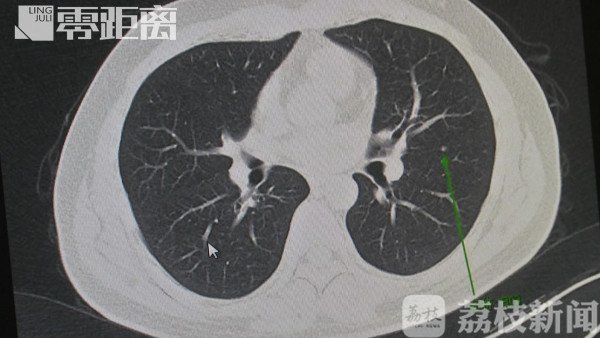

王俊医生介绍,目前分为磨玻璃结节、实性结节,介于两者中间的,称为混合性结节。有一些磨玻璃结节,慢慢地长实以后,甚至出现了中心的一些空洞,这个时候,中间有空泡的症状,这些都是要高度警惕的。

磨玻璃结节在CT影像上表现为高密度、云雾状,就像磨砂玻璃一样,如果其中还伴有实性成分,这一类的患者就要高度警惕了。如果是小于5毫米的实性结节,良性的概率就非常大。(敲黑板)简单而言,结节直径越大、长得越“古怪”,恶性可能性就越大。